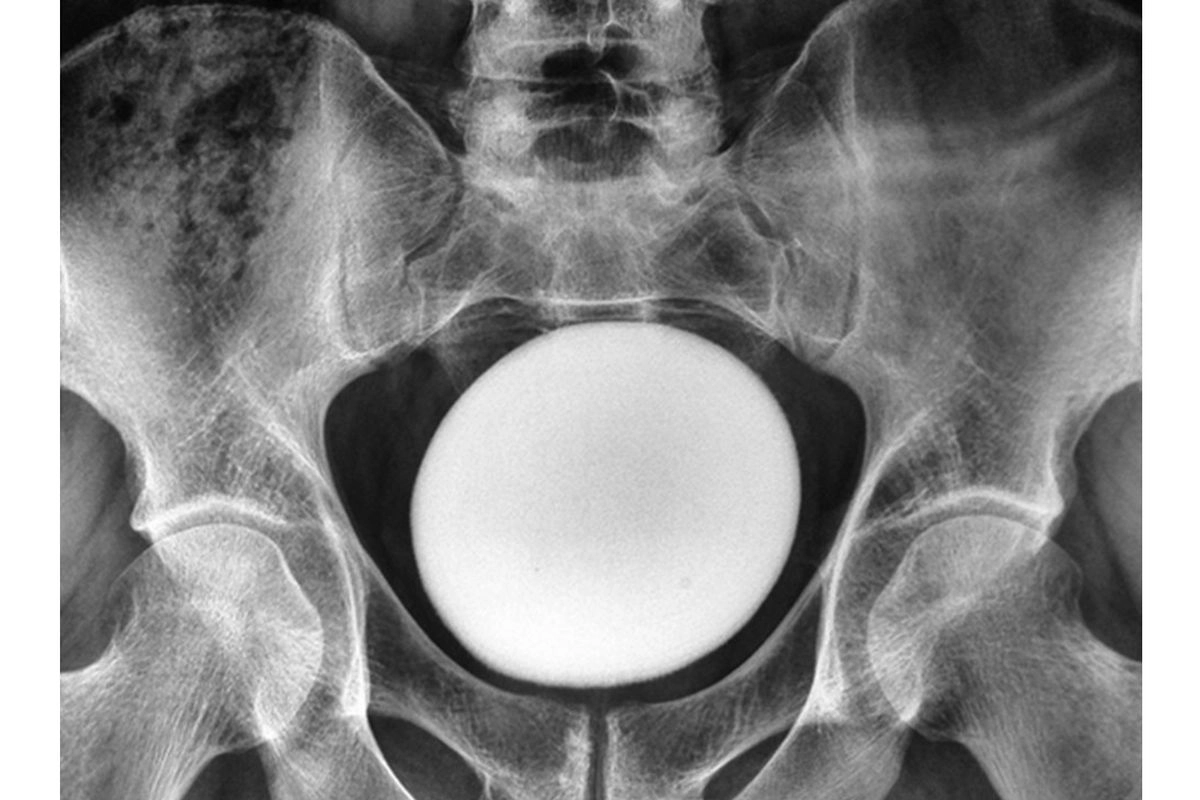

Tangkapan layar dari Jurnal Nephro-Urology Monthly soal seorang pria hanya mengeluh tidak nyaman di kandung kemih, tetapi dokter menemukan batu saluran kemih raksasa seberat 826 gram yang tumbuh diam-diam tanpa gejala berat.(Tangkapan layar dari Jurnal Nephro-Urology Monthly)

Pemeriksaan ultrasonografi menunjukkan massa berbentuk oval dengan diameter sekitar 11 sentimeter.

Operasi kemudian mengungkap batu dengan ukuran sekitar 13 × 10 × 8 sentimeter dan berat 826 gram, jauh lebih besar dibandingkan batu saluran kemih pada umumnya.

Batu tersebut bahkan digambarkan menyerupai telur burung unta dan memenuhi hampir seluruh ruang kandung kemih pasien.

Dokter mendiagnosis kondisi ini sebagai giant bladder stone atau batu kandung kemih raksasa.